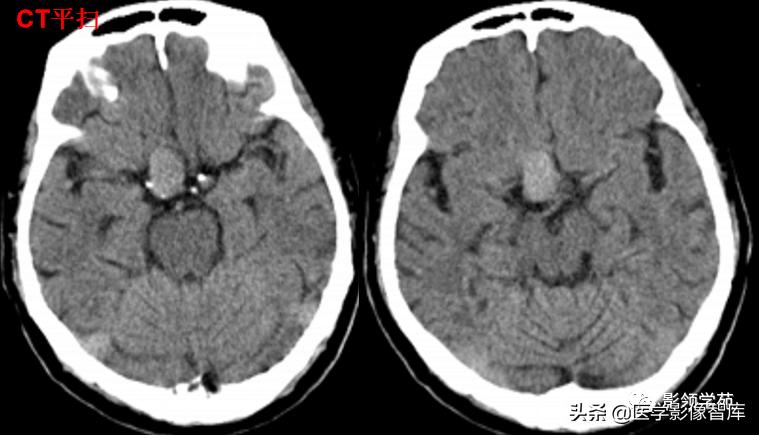

女 61岁 反复头晕3年余

鞍上可见一类圆形均匀稍高密度灶,CT值约47HU,

边界清楚,其内见一小点片状钙化灶;继发鞍上池受压伴变性。

鞍区占位肿块,呈等T1等T2信号,信号均匀,边界清楚。

病灶呈均匀、显著强化(馒头样),以宽基底与前颅窝底相连,

冠状位和矢状位见脑(硬)膜尾征;

肿块突入鞍上池,向上推压视交叉,后缘紧邻垂体柄,与双侧颈内动脉相邻。